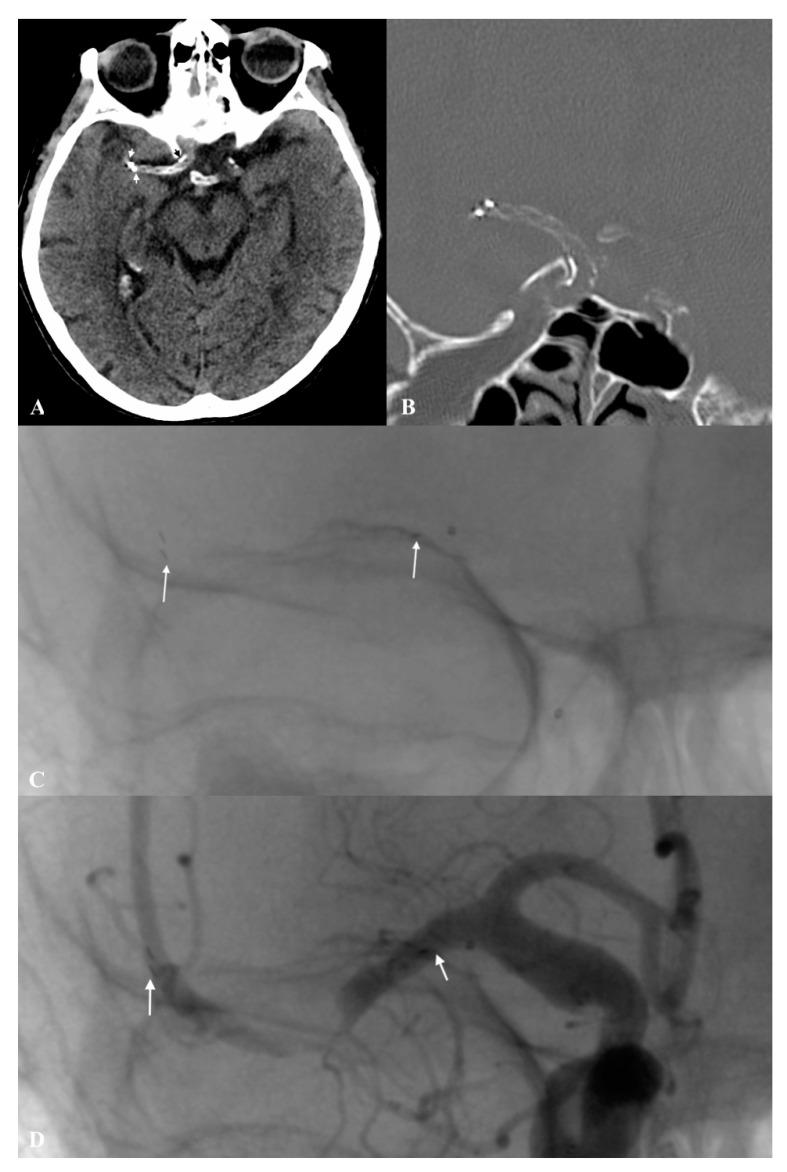

The inadvertent detachment of stent retrievers during mechanical thrombectomy is an extremely rare but feared complication associated with poor clinical outcomes. We discuss management considerations after an unexpected disconnection of the pRESET stent retriever during mechanical thrombectomy, based on clinical experience and mechanical and phantom studies.

We present a clinical course of rare accidents of stent-retriever separation inside an intracranial vessel that occurred in patients in a comprehensive stroke centre between 2018 and 2020. We designed a phantom study to assess the Tigertriever's ability to remove a detached stent retriever from intercranial vessels. In the mechanical study, several types of stent retrievers were evaluated in order to find the weakest point at which detachment occurred.

Two patients (~0.7%) with inadvertent stent-retriever detachment were found in our database. Failed attempts of endovascular removal with no recanalization at the end of procedure were reported in both cases. mRS after 3 months was three and four respectively. In the mechanical study, the Tigertriever was the most resistant to detachment and was followed by Embotrap > pRESET > 3D Separator. In the phantom study, the pRESET device detached in a configuration resembling the M1 segment was successfully removed with the Tigertriever.

Conservative management of the inadvertent detachment of stent retrievers during mechanical thrombectomy in large vessel occlusion may be acceptable in order to avoid further periprocedural complications after unsuccessful device removal attempts. Based on the phantom and mechanical studies, the Tigertriever may be a useful tool for the removal of detached pRESET devices.